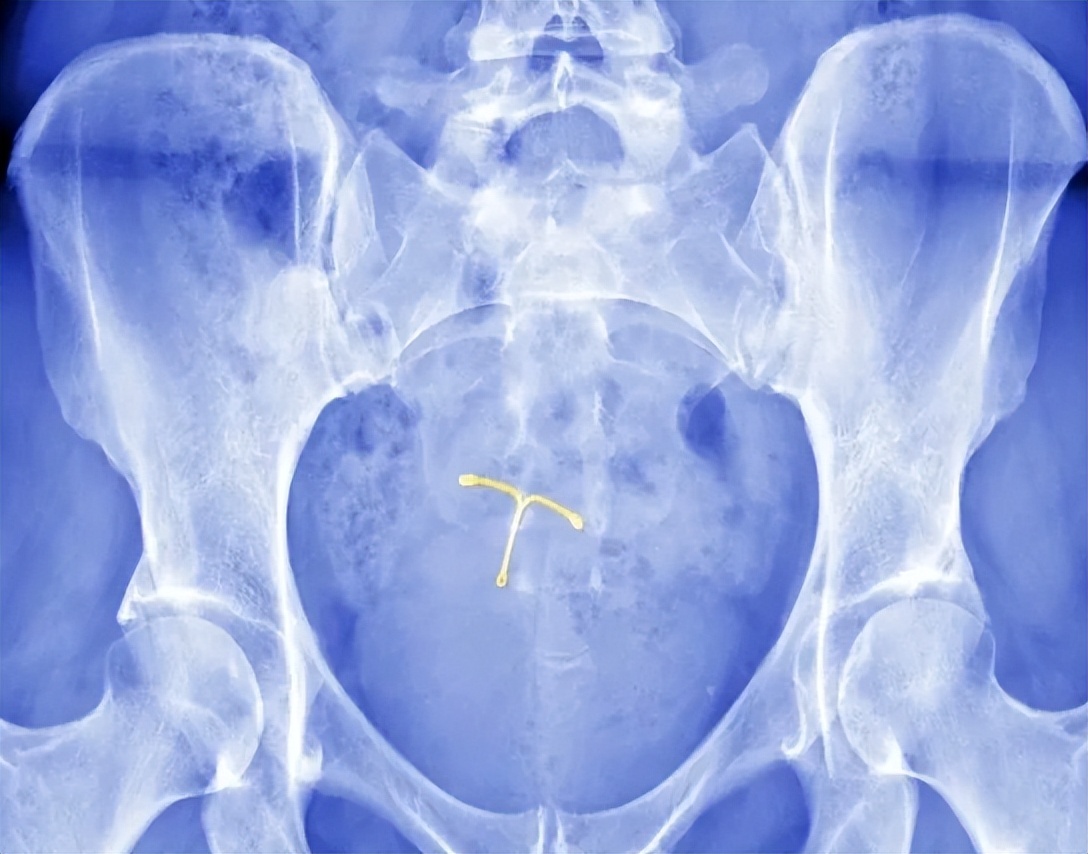

形状上比较常见的有单环型、麻花型、V字型、T字型等,也可根据子宫大小定制宫形环。

比如有剖腹产史的女性,可选择T型环,而顺产史女性,可选择圆形环、宫形环。